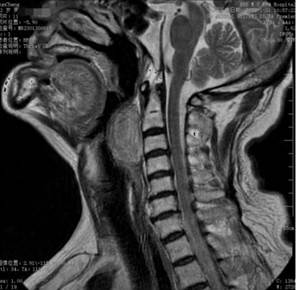

据悉,72岁的孙大爷呼吸困难及吞咽不畅感有近1年的时间,最近两个月加重,严重影响了生活质量。多方诊治无效后,孙大爷来到ac米兰官网中文网站四院行相关检查后,发现口咽至喉咽部长了一个巨大的肿物,MRI显示肿物位于咽后间隙内。

(图1、2核磁检查见口咽至喉咽巨大肿物)